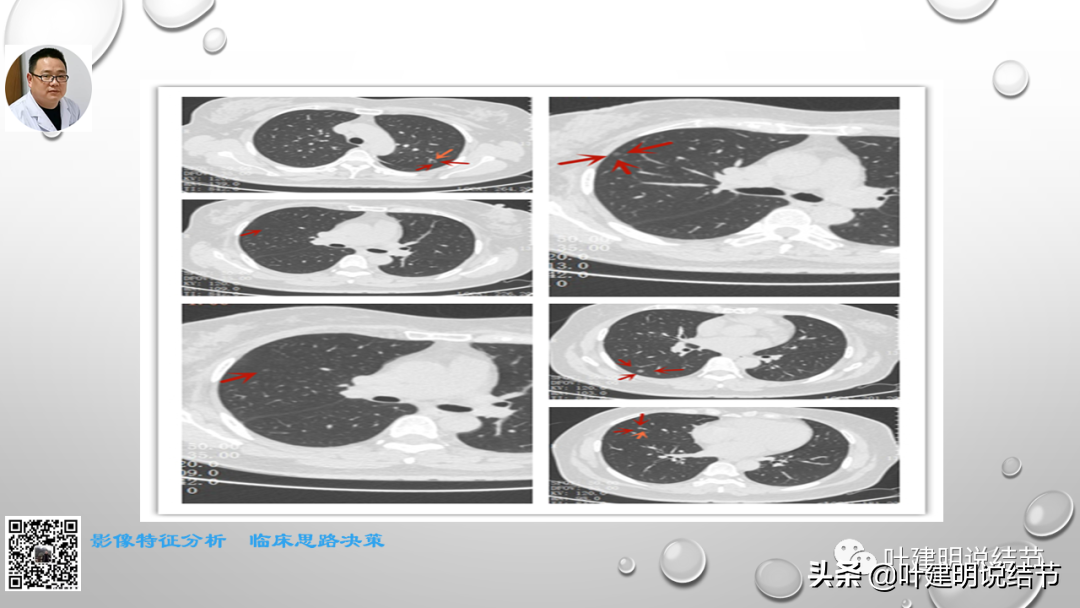

这次讲课的第三部分是阐述对于磨玻璃为表现的早期肺癌自己的观点与理念以及相应思考的精髓部分。也是我一直坚持不懈宣传、普及的思想。也许目前只是想法而已,因科研水平能力所限,无法转换为循证依据来证实其正确性。但我想我们的呼吁总也会引起有相关科研能力同道的注意,从而在未来得以验证并改写指南或出台专门针对肺磨玻璃结节为表现的早期肺癌的诊疗规范或指南。如果真有这种事情发生,那么自己的所作所为将是意义非凡的!